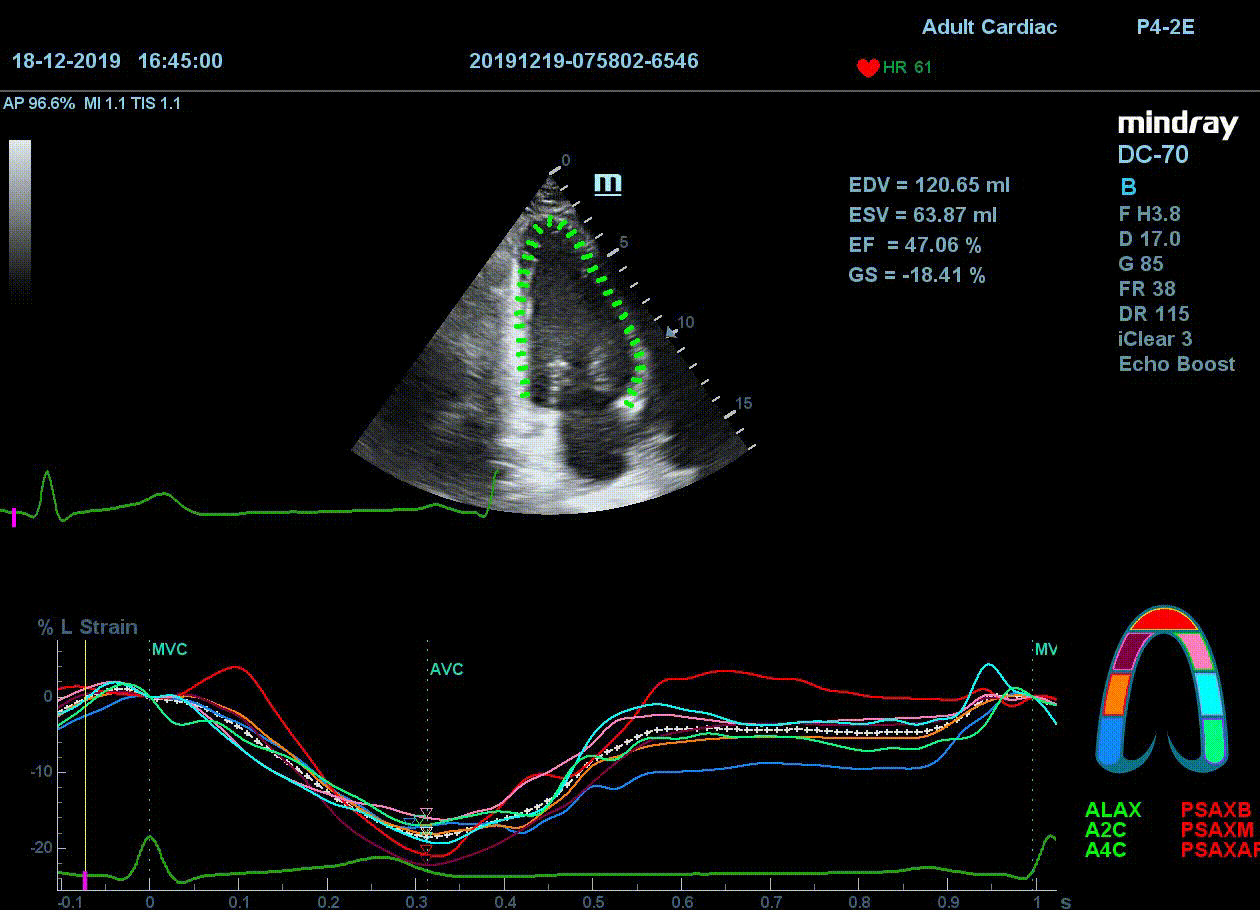

Как работать с данным методом? Для Longitudinal Strain необходимо записать видео петли апикальных сечений в память прибора: 4С, 3С, 2С. Для повышения качества трекинга рекомендуется производить запись на выдохе пациента. Затем произвести разметку по линии эпикарда, перикарда и центра миокарда. Нажатием кнопки «начать слежение» активируется программный алгоритм, видео петля оживает вместе с размеченными точками-speckle’ами. При необходимости производится коррекция. После анализа всех трех сечений можно получить данных продольной деформации как в среднем значении, так и по каждому сегменту миокарда левого желудочка. Нормальным показателем считается Longitudinal Strain -20%. Нижней границей -14%.

Видео примеры на приборе Mindray DC 70